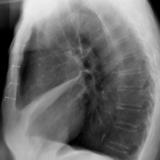

Case 1 Lateral